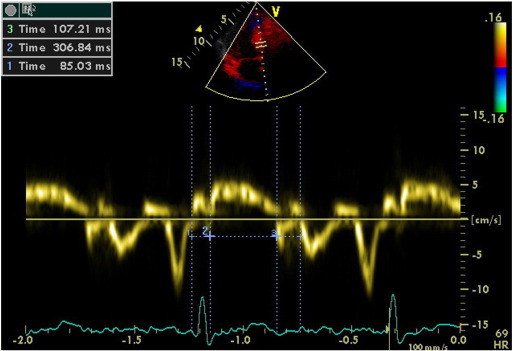

We calculated TDI-derived regional MPI using the values of both systolic and diastolic parameters at LV septal base (Fig. 3), then lateral base and found that MPI values were significantly abnormal at both region in group II compared with those in group I and group III (both p < 0.0001, Table 3). However, despite abnormal MPI in both hypertrophied LV walls, septal MPI was more severely impaired compared with that of lateral MPI in group II (p = 0.012). Septal MPI was correlated moderately with septal wall thickness (r = 0.447, p < 0.001, Fig. 4).

Fig. 3. Evaluation of isovolumetric contraction time, contraction time and isovolumetric relaxation time of the LV septal base by tissue Doppler imaging in a hypertensive patient with left ventricular hypertrophy (MPI = 62). |